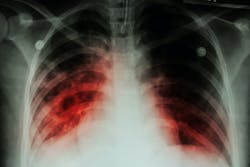

Effective TPT in people at highest risk of progression safely reduces the likelihood of developing TB disease. This includes individuals exposed to multidrug- or rifampicin-resistant TB (MDR/RR-TB).

The updated guidance will avail of the latest evidence and best available practices on TPT regimens for individuals of all ages in contact with TB patients and dosing schedules. It will also incorporate current recommendations on screening strategies to rule out TB disease ahead of starting TPT, and the use of tests of TB infection.